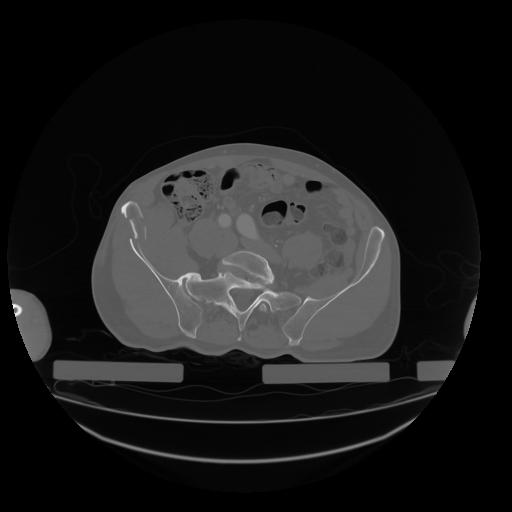

28 CUERPO,CE,Vol,2.0,CUERPO,,